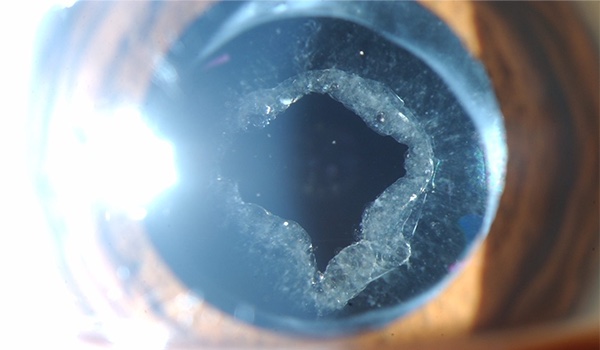

Cirugía de catarata e implante de lentes intraoculares

Una cirugía de catarata en la actualidad es un proceso relativamente simple y muy seguro, con resultados positivos en aproximadamente el 99% de los casos. Su realización es bajo anestesia local en forma de gotas, y muchas veces con ligera sedación para aligerar el miedo y la ansiedad. Tiene una duración de más o menos 15 minutos, y una recuperación visual menor a una semana, aunque puede tardar 30 días en estabilizarse completamente. Se realiza primero en el ojo más afectado, y sus resultados son para toda la vida. Las cirugías más complejas tienden a ser las que se pospusieron por más tiempo. Te invitamos a apuntar todas tus dudas previo a la consulta para tener una conversación extensa que tenga como objetivo tu confianza y tranquilidad.

Si deseas saber más acerca de la cirugía de cataratas, haz clic aquí